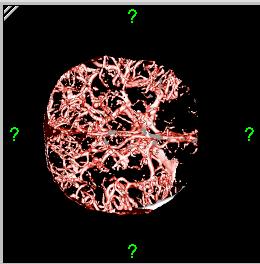

الأشعة المقطعية أو التصوير المَقْطَعي الحاسوبي Computed tomography نظام تصوير بالأشعة السينية، يُسْتخدم لتصوير مختلف أجزاء الجسم مثل الرأس والقلب والبطن. ويستعين الأطباء بالتصوير المقطعي الحاسوبي على تشخيص الأمراض وعلاجها. وتسمى هذه التقنية أيضًا التصوير المقطعي المحوسب أو التصوير المقطعي المحوري المحوسب.

وللحصول على صورة أشعة مقطعية، يرقد المريض على طاولة تمر من خلال آلة فحص دائرية، تسمى المِسْند. وتوضع الطاولة بحيث يكون العضو المراد فحصه واقعًا عند منتصف المسند. وعن طريق أنبوب على المسند، تخرج أشعة سينية مخترقةً جسد المريض، ثم تدخل إلى مكشافات خاصة تقوم بتحليل الصورة التي ظهرت. ويدور المسند حول المريض للحصول على كثير من الصور من زوايا مختلفة. وبعد ذلك، يعالج الحاسوب المعلومات الآتية من المكشافات، لينتج صورة مقطعية مستعرضة على شاشة فيديو. وعن طريق تحريك الطاولة داخل المسْند، يمكن للأطباء الحصول على العديد من الفحوص للعضو نفسه، أو للجسد كله.

ويستعمل الأطباء فحوص التصوير المقطعي الحاسوبي لتشخيص كثير من الحالات مثل الأورام والإصابات وتجلطات الدم وكسور العظام. ويساعد التصوير المقطعي الحاسوبي أيضًا في معالجة بعض الأمراض، التي قد تتطلب جراحة بطريقة أخرى. فمثلا،ً يمكن للأطباء استعمال التصوير المقطعي الحاسوبي لإرشادهم إلى إدخال القثطار (أنبوب رفيع) إلى خُرّآج في الجسم لسحب الصديد من المنطقة الملوثّة.